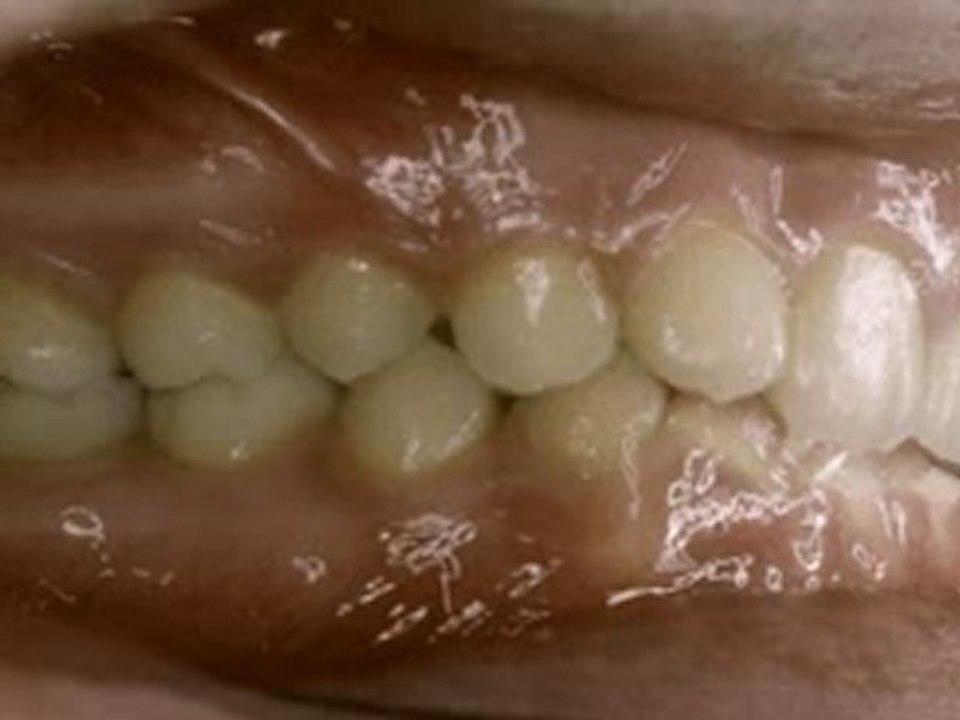

Yan açık kapanış tedavisi